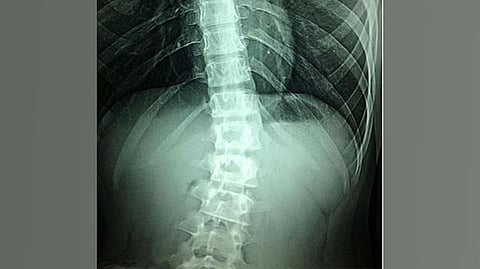

Vertebral compression means that the spine is compressed, causing a fracture in one of the vertebrae. Vertebral compression fractures (VCFs) occur easily in people with osteoporosis, and affect older women in particular.

Vertebral compressions do not necessarily result in distinct symptoms. Imaging is needed to detect these spinal fractures. If more people were diagnosed, many fractures, much suffering and heavy costs could be avoided.

Efforts to prevent fractures in older people vary around the country. In some regions, but not all, there are established “fracture liaison services,” as they are known in Sweden. These ensure that investigations of fractures are structured in a way that greatly reduces the risk of repeat fractures. When elderly patients have suffered fractures, their hip and lumbar spine bone density is examined with the dual-energy X-ray absorptiometry (DXA) method, to find out if they need treatment for osteoporosis. DXA can then also be used to get a side view of the chest and lumbar spine, with a method called vertebral fracture assessment (VFA), in which the height of the vertebrae is analyzed.